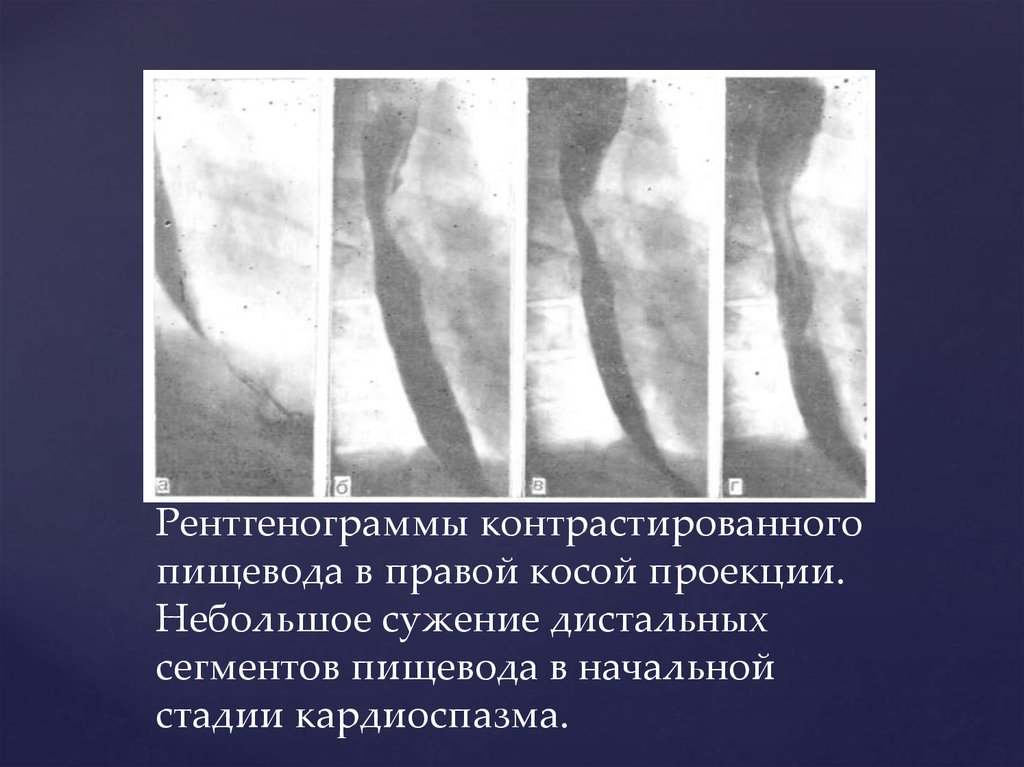

Рентгеноскопия желудка с контрастным веществом

Правильный диагноз. Ангиография. Рентген шейного отдела с контрастом